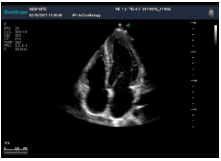

不同的探頭對(duì)應(yīng)于不同的臨床領(lǐng)域,不同的探頭頻率也應(yīng)用于不同的人體組織。超聲波在人體中的衰減與探頭頻率有關(guān),探頭頻率越高,穿透力越弱,分辨率越高,而探頭頻率越低,穿透力越強(qiáng),分辨率越低。因此在檢查淺表器官時(shí)應(yīng)選用高頻探頭,而檢查深部臟器時(shí)則選用穿透性強(qiáng)的低頻探頭。